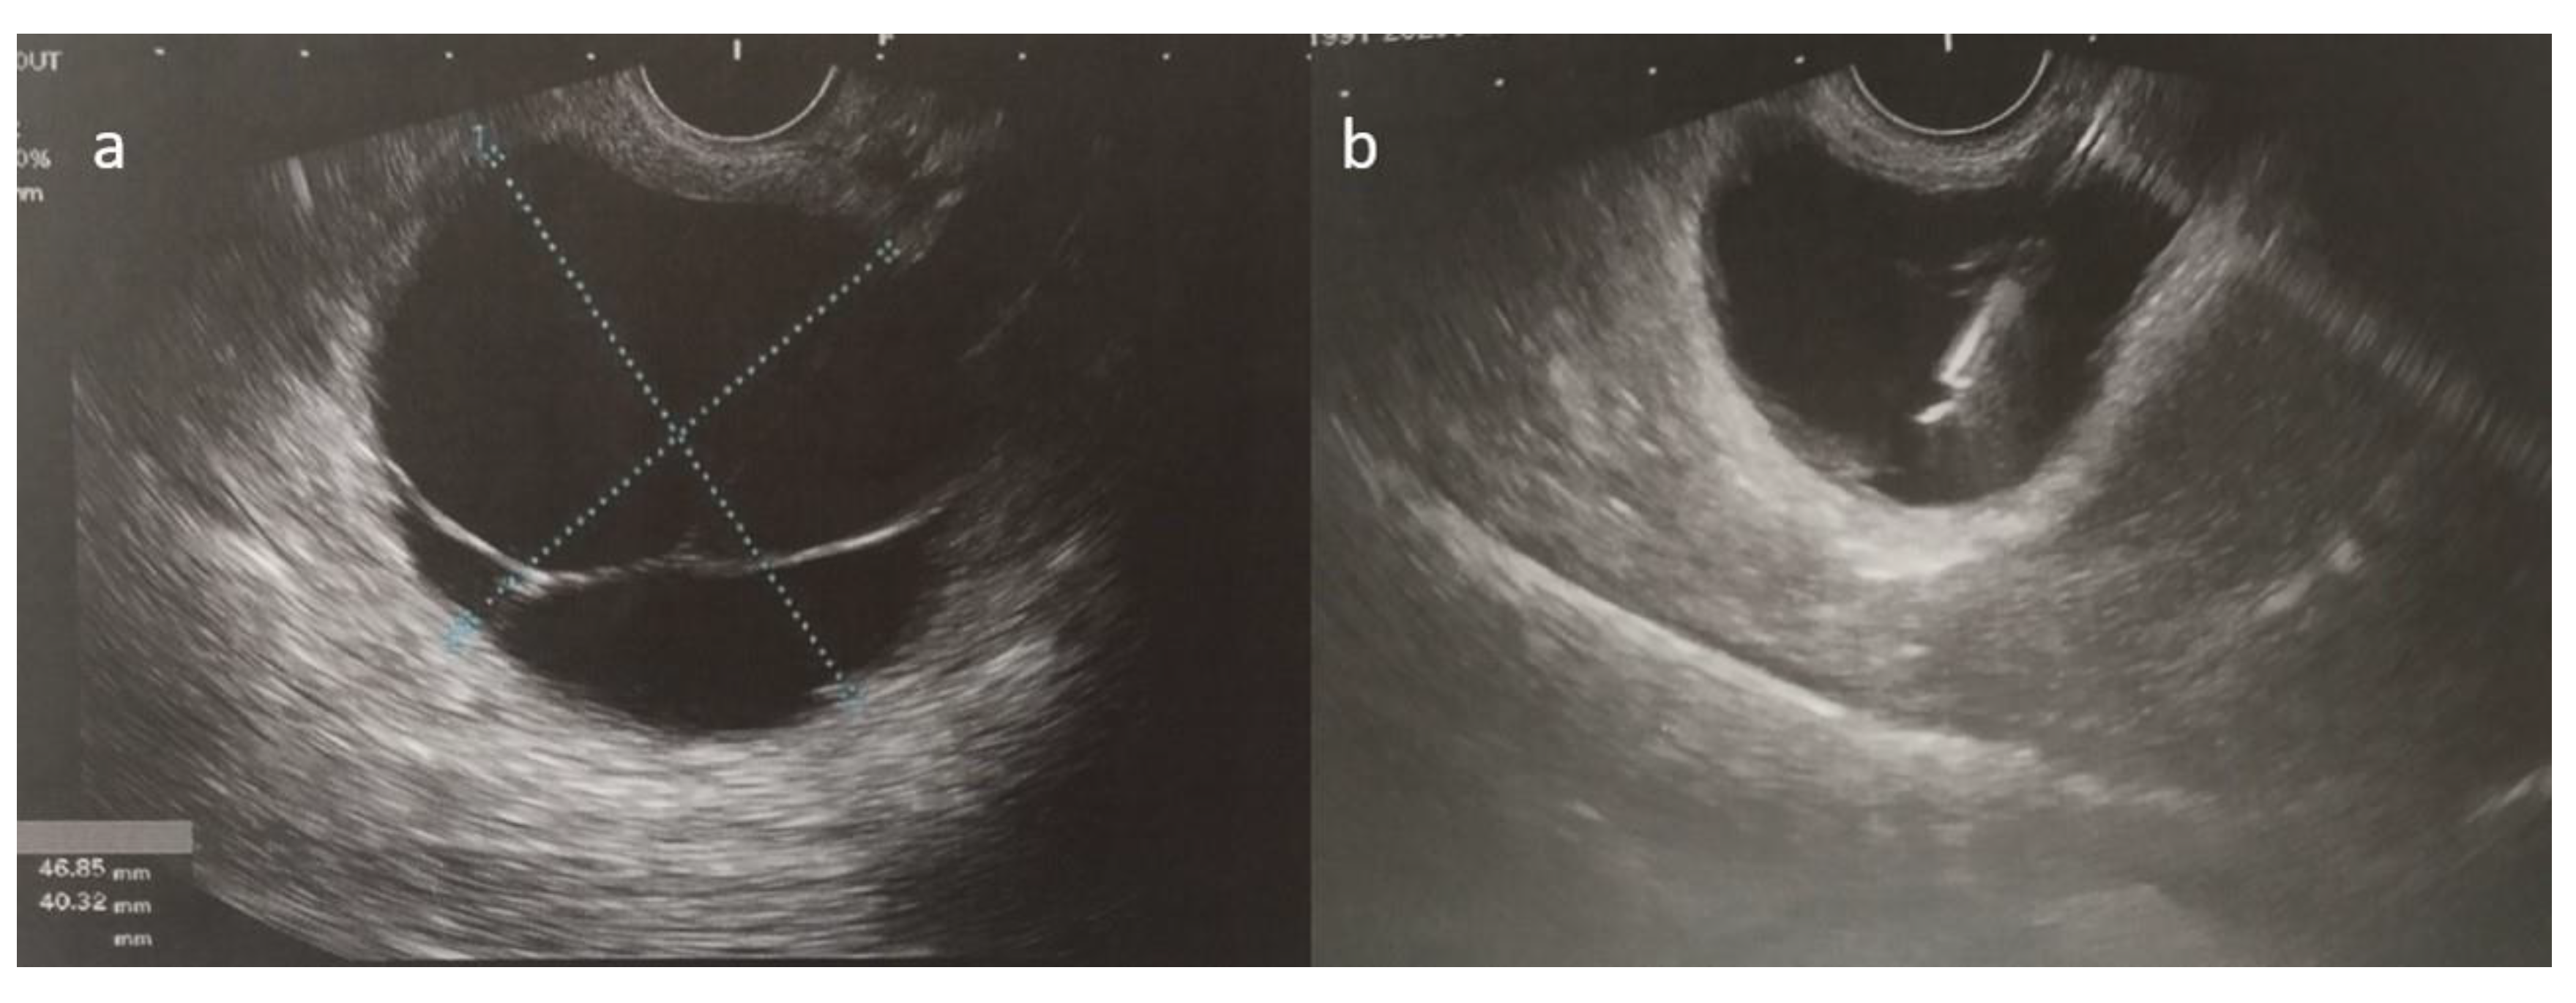

As her symptoms worsened over time, the patient ultimately presented to the emergency department with persistent epigastric and lower back pain. Following a complete clinical, laboratory, and imaging workup, the pancreatic cyst was confirmed through an ultrasound-guided fine-needle aspiration, which suggested a mucinous cystic neoplasm with no signs of dysplasia (Figure 5). The patient then underwent a laparoscopic distal pancreatectomy and splenectomy. Initially, the surgery was uneventful, and the patient was extubated and monitored in the ICU for one day before being transferred to the surgical ward.

Figure 5.

(a,b) Ultrasound-guided fine-needle aspiration of the cystic fluid was performed.